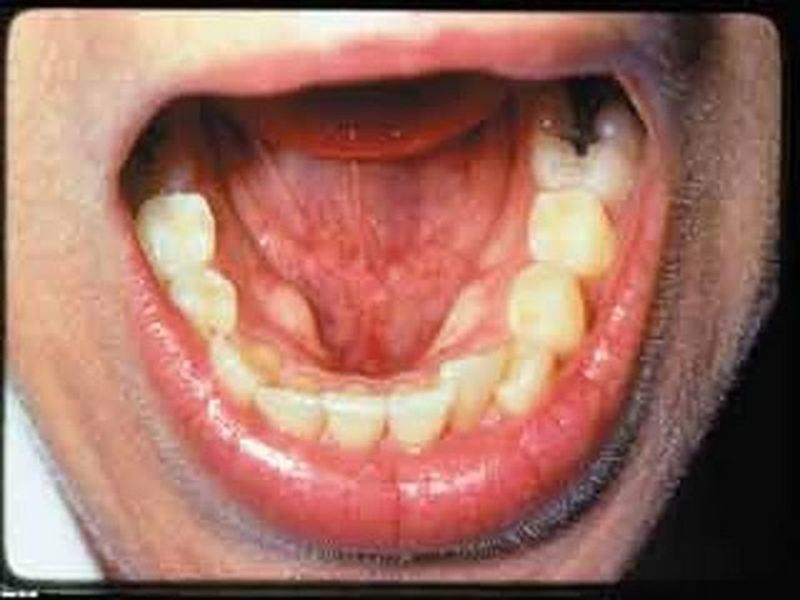

उदयपुर. लगातार बढ़ते हेड नेक (मुंंह व गले) कैंसर का अब भी एमबी हॉस्पिटल में परम्परागत तरीके से ही उपचार चल रहा है। नाक कान व गले (इएनटी) में कैंसर के मरीजों की संख्या लगातार बढ़ रही है, लेकिन यहां उनके उपचार सर्जरी ही है। हालात यह है कि मरीज या तो सर्जरी करवाते हैं या कार्बन डाई आक्साइड लेजर उपचार के लिए अपनी जेब ढीली कर जयपुर या अहमदाबाद की राह पकड़ते हैं।

तीन साल में सात सौ से अधिक मरीजतीन साल में हेड नेक के कैंसर के एमबी हॉस्पिटल में करीब सात सौं से अधिक सर्जरी हो चुकी है। यहां पहुंचे मरीजों की संख्या तो एक हजार से पार थी। ये लेजर मशीन यानी कार्बन डाइ आक्साइड लेजर गले या मुंह के कैंसर में ट्यूमर को जला कर निकाल देता है, जबकि अभी एमबी हॉस्पिटल में चीरा लगाकर सर्जरी से काम चलाया जा रहा है। सर्जरी में औसतन 4 से 5 घंटे लगते हैं। कई बार तो सुबह से शाम यानी सात घंटे से अधिक समय लग जाता है। यदि लेजर मशीन हो तो दो से तीन घंटे में इस प्रक्रिया को अपनाकर लेजर ऑपरेशन किया जा सकता है। इससे डॉक्टरों का काफी समय बच सकता है। इस लेजर मशीन की कीमत करीब एक करोड़ रुपए है। इसे किसी भी मरीज के मुंह या गले के ट्यूमर पर टारगेट कर इसे जलाने की प्रक्रिया अपनाई जाती है।

प्रत्येक मरीज को लगता है 50 हजार से दो लाख तक का फटकाजो मरीज यहां सर्जरी नहीं करवाकर जयपुर, अहमदाबाद या अन्य बाहरी किसी निजी हॉस्पिटल में लेजर उपचार के लिए पहुंचता है तो उसे 50 हजार रुपए से लेकर करीब दो लाख रुपए तक का फटका लगता है। यह मशीन यहां नाक, कान व गला (इएनटी) विभाग में मरीजों की संख्या को देखते हुए जरूरी मानी गई है, लेकिन इसे अभी तक यहां नहीं लाया गया है।